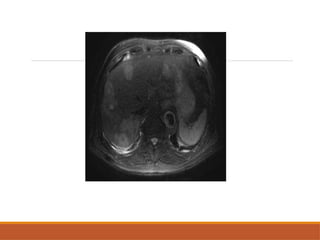

• #5 This is the axial cect image in arterial pjhase showing the well defined uniformly enhancing lesions – this is a case of hypervasculat metastasia from melanoma